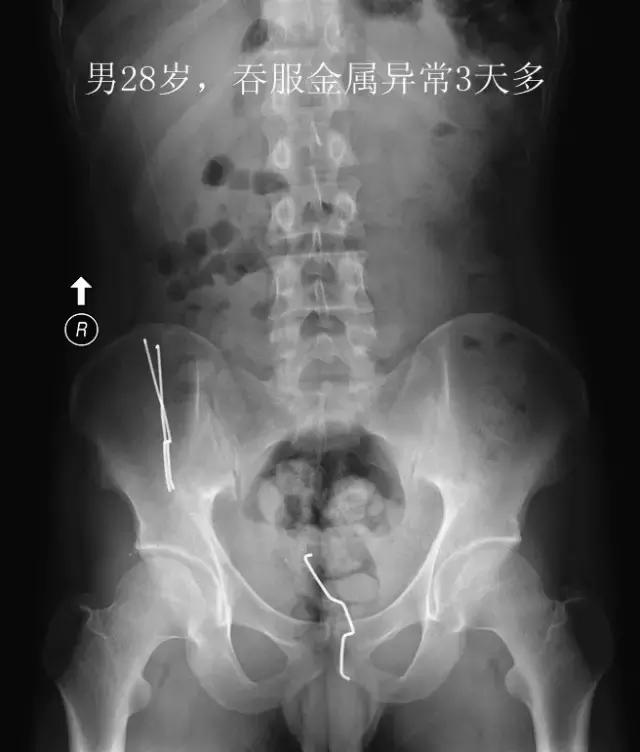

最后,是“看图识物”环节,请大家辨认下面三张图中的物体,欢迎在留言区发表你的看法哦。